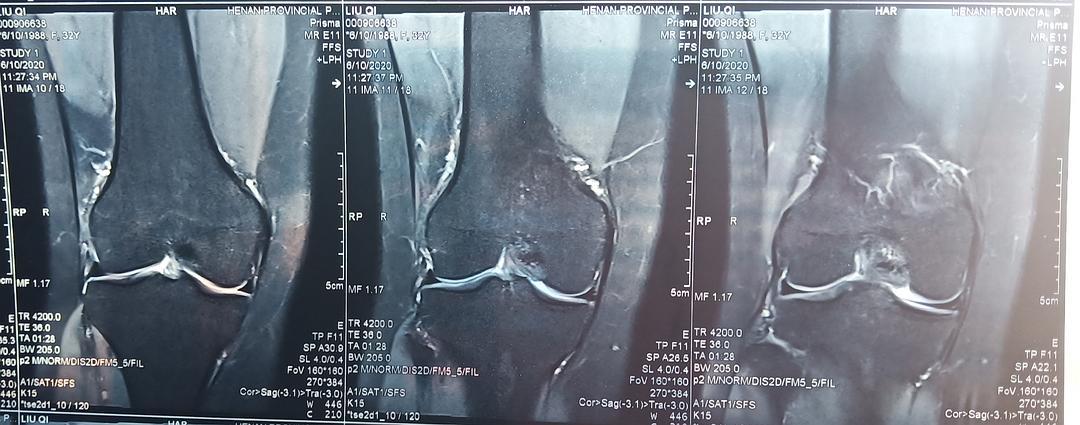

膝关节核磁共振读片

膝关节的核磁片子,半月板有损伤,自己也看不太懂,帮我

【关节影像】膝关节的磁共振(mri)解剖表现

磁共振成像优势---膝关节